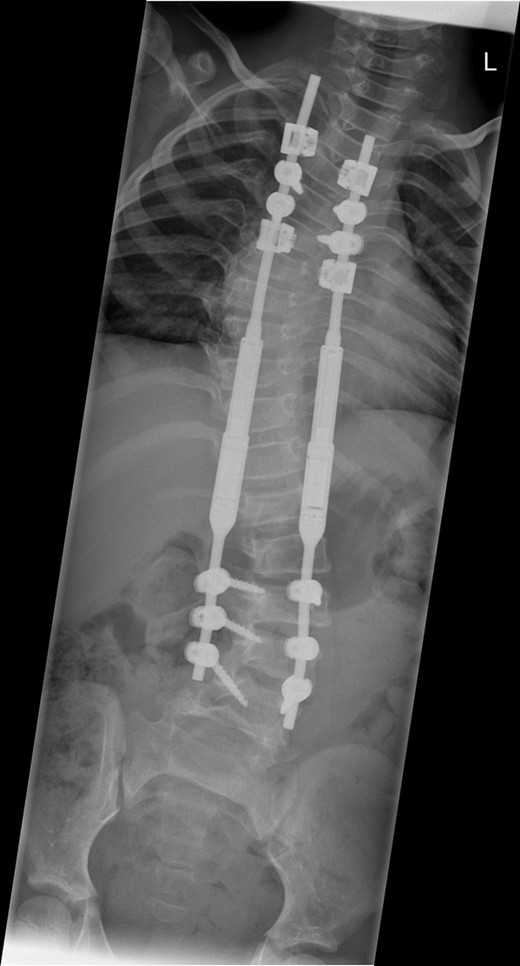

Between the ages of 4 and 6 years, the curve increased rapidly leading to a significant curve measuring 80° in the thoracic spine and 65° in the thoracolumbar spine with a T1–S1 height of 232 mm and T1–T12 height of 150 mm (Fig. 1). A decision was made to intervene operatively and posterior instrumentation with MCGR was performed. Special consideration was given to her bone fragility. Following 4.5 years of bisphosphonate therapy, her last bone mineral density (BMD) assessment by dual energy X-ray absorptiometry before surgery was normal. Her lumbar spine BMD Z-score was +1.5 and the total body less head BMD Z-score was also +1.5. Thus, at age 6 years, a construct of three paired sets of pedicle screws were placed at L2–L4 distally and a combination of pedicle screws at two levels (T4 and T5), with an outer square of sublaminar bands passed under the third and sixth ribs, was placed proximally. The instrumentation used was a 4.5 Expedium System (DePuy Synthes, Raynham, MA, USA) and the Silc Sublaminar Banding System (Globus Medical, Audubon, PA, USA). Post-operative radiographs (Fig. 2) showed good spinal balance and correction of deformity, but fractures of the right 5th and 10th ribs were seen posteriorly at the junction of the rib and transverse process. Following 8 weeks of spinal cast jacket protection, a CT scan showed the rib fractures to have healed. After instrumentation the thoracic curve angle measured 38° and the thoracolumbar curve measured 30°, with a T1–S1 height of 247 mm and a T1–T12 height of 160 mm.

An immediate post-operative whole spine radiograph demonstrating the spinal construct with the MCGR rods (measuring 38° in the thoracic curve and 30° the thoracolumbar curve with a T1–S1 height of 247 mm and a T1–T12 height of 160 mm).